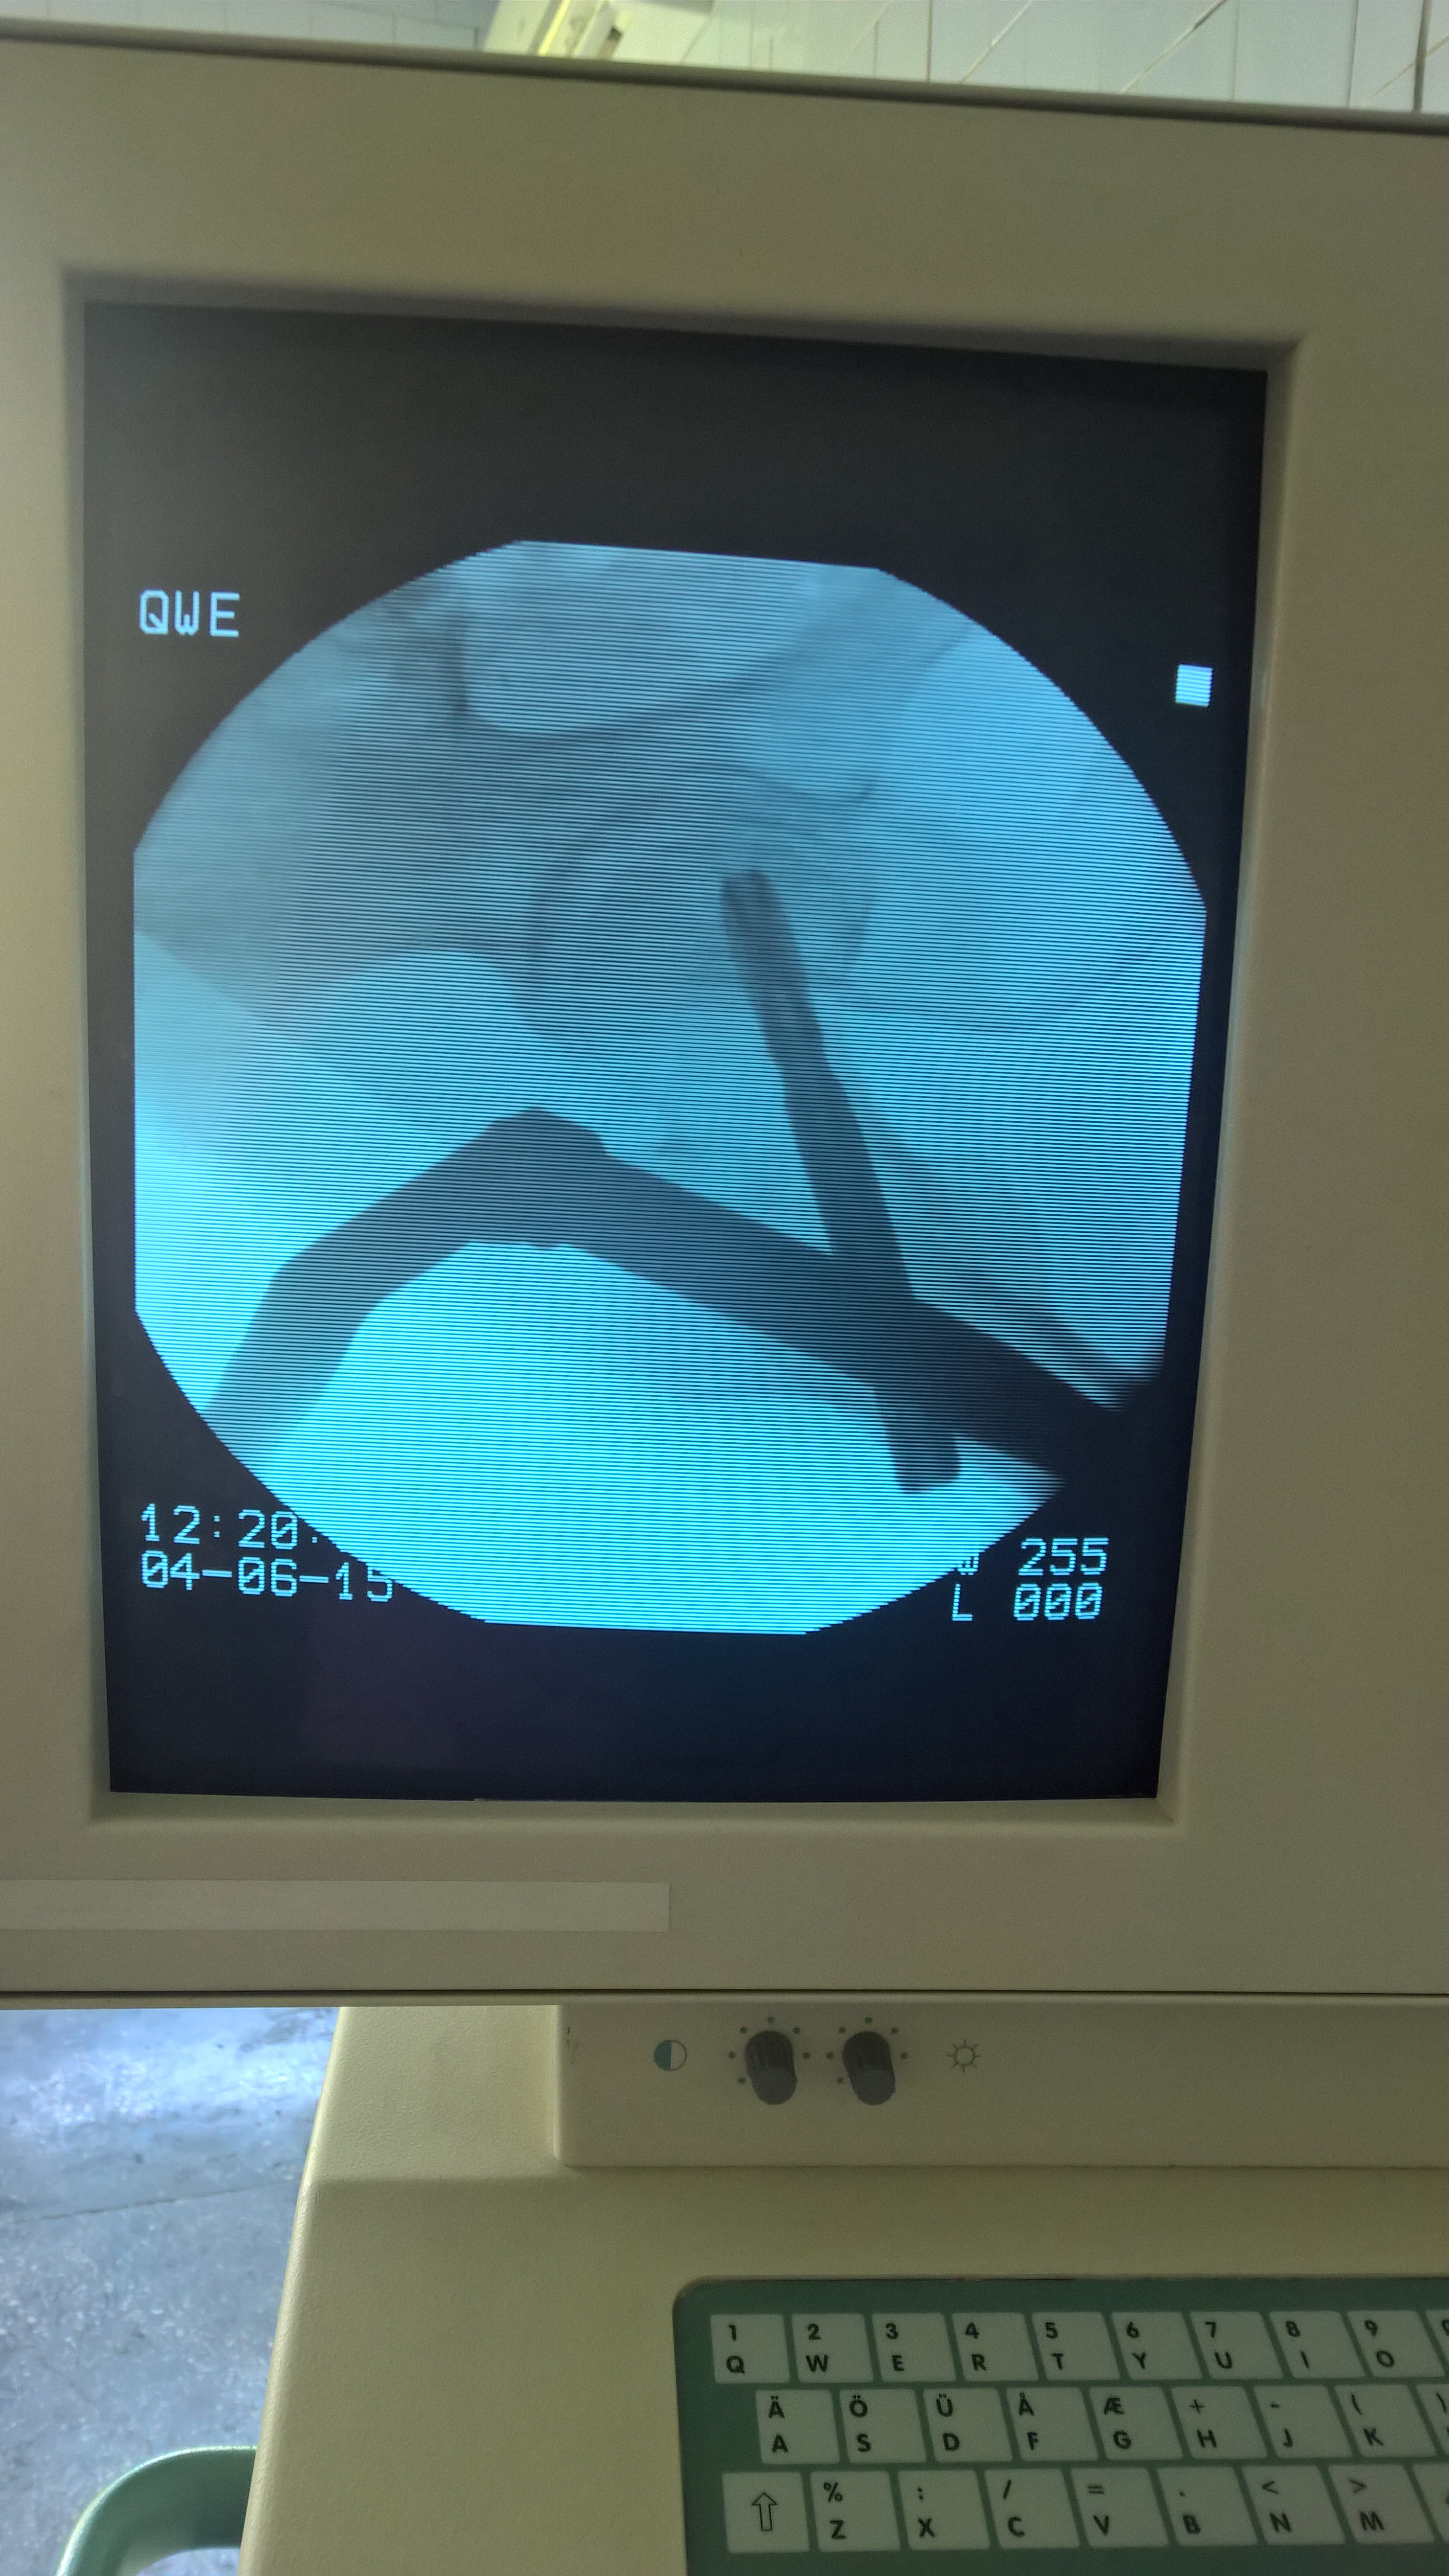

Современная методика лечения переломов бедренной кости - система PFNA (Proximal Femoral Nail Antirotation)